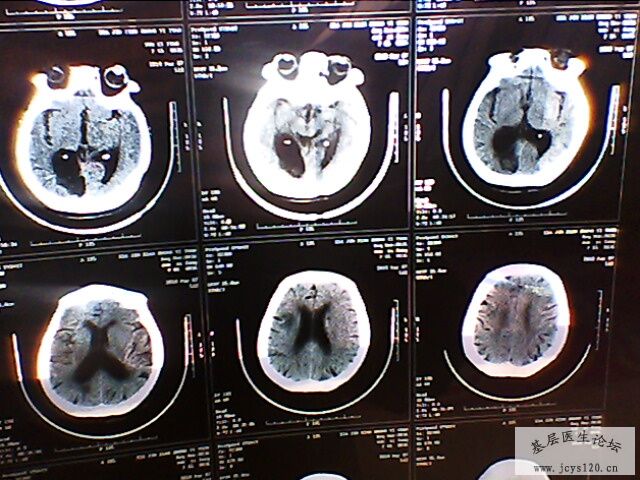

右侧肢体活动障碍半小时

患者,女,65岁,在半夜起来上厕所时发现右侧肢体不能活动,无头痛,无恶心呕吐,无意识障碍,无大小便失禁,持续大概十分钟后症状消失,唯感觉右侧肢体稍无力,为进一步检查和治疗来诊。

查体:血压160/90 mmHg 心率80次/分

自主体位,神志清楚,语言流利,双侧瞳孔等大等圆,对光反射灵敏,伸舌居中,心肺听诊、腹部检查无异常,四肢活动正常,肌力正常,病理征未引出,生理反射存在。

既往史:既往体健,三天前在家因为头晕测血压200/100mmHg ,在家口服药物(复方利血平)后血压降至正常。无心脑血管疾病病史。